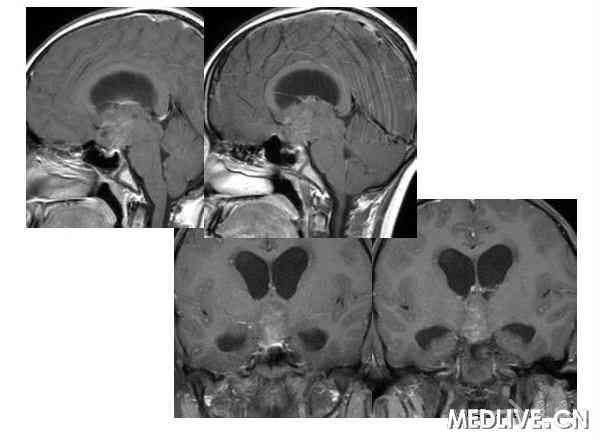

经典病例: 男性,15岁,身材发育迟缓,多饮多尿3年身材矮小

男性,15岁,身材发育迟缓,多饮多尿3年身材矮小 病理症阴性

鞍区生殖细胞瘤临床症状:多饮多尿,视力障碍 身材矮小,性早熟。

解答详情: 生殖细胞瘤由原始的生殖细胞衍生而来,好发于松果体区,其次为鞍上池。肿瘤多发生于男性青少年,位于鞍上生殖细胞瘤则以女性多见。生殖细胞瘤对放射线非常敏感。该瘤通常无包膜、无钙化、出血、坏死或囊性变,属低度恶性肿瘤,多呈浸润性生长,常有不同程度和形式的转移,易向蛛网膜下腔及脑室系统种植、播散。组织学上,肿瘤主要含有两种细胞成分:上皮样细胞和淋巴样细胞。 1、CT表现:  ①肿瘤最常见于松果体区,位于鞍上区肿块常累及漏斗;  ②CT平扫多呈等密度或稍高密度肿块,无出血、坏死及囊性变,可分叶,但境界清楚;瘤体本身钙化少见,典型松果体区生殖细胞瘤常见肿瘤包埋松果体钙化灶。  ③增强扫描呈中等至明显的均匀强化。  ④室管膜下转移可表现为沿脑室壁线状或条片状强化,沿脑脊液向蛛网膜下腔播散表现为脑表面、脑池的线状或结节状强化。   2、MR表现:  ①最常见于松果体区,也常见于鞍上,可同时或单独存在。②T1加权为略低信号或等信号,T2加权常呈等信号或高信号。③增强后;呈明显均匀一致强化,并能发现沿脑脊液或室管膜转移的病灶。鉴别诊断  1、颅咽管瘤:多为囊性或囊实性肿块,钙化多见。纯实性者可呈稍高密度,并可强化,与生殖细胞瘤不易鉴别、  2、星形细胞瘤:一般肿瘤较大,密度偏低,后期可出血,肿瘤通常位于下丘脑,并沿视交叉或视束延伸,可在眼眶内形成肿块。  3、垂体瘤:发生于鞍内,但可向鞍上生长,小儿罕见,肿瘤易出血、坏死,鞍底骨质变薄、下陷,海绵窦常受累。 生殖细胞瘤。4、脑膜瘤:好发于成人,儿童罕见,肿瘤部位偏前,伴骨质增生、硬化及蝶窦过度气化。